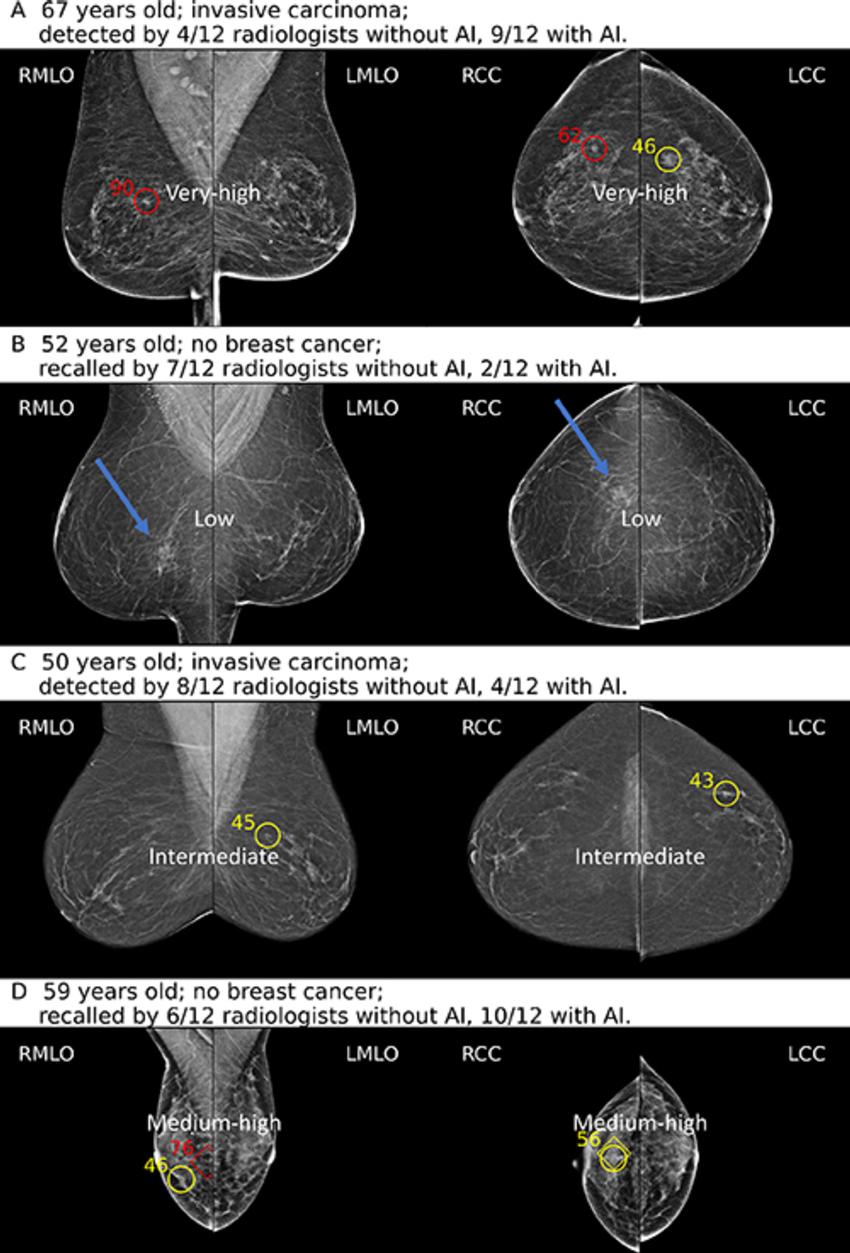

Figure 2. (A) Screening mammograms in a 67-year-old woman with a mass in the upper outer quadrant of the right breast. The AI tool classified this examination as very high risk, with a maximum region score of 80 or higher at the cancer location. (B) Screening mammograms in a 52-year-old woman without breast cancer who was recalled by seven of the 12 radiologists when reading without AI support. The AI tool classified this examination as low risk, with a maximum region score under 40. (C) Screening mammograms in a 50-year-old woman with an ill-defined mass in the upper outer quadrant of the left breast, diagnosed as invasive mixed ductal/lobular carcinoma. The AI tool classified this examination as intermediate risk, with a maximum region score between 40 and 59. (D) Screening mammograms in a 59-year-old woman without breast cancer. The AI tool classified this examination as medium-high risk, with a maximum region score between 60 and 79. The AI examination category and AI-marked regions with region scores are shown as in the reader study, with diamonds indicating calcifications and circles indicating soft tissue lesions.